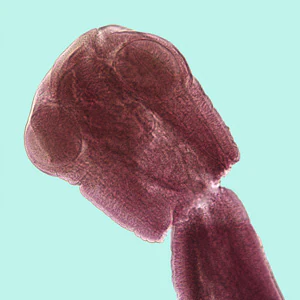

Adults are 40-150 cm long and the strobila can contain more than 400 proglottids. Immature proglottids are about three times broader than long, and mature but non-gravid proglottids are nearly square. Gravid proglottids are longer than wide and contain a parauterine organ that encloses a mass of eggs. The scolex has four suckers, but no rostellum or hooklets.

Numerous vertebrates can serve as the second intermediate host, in which the infective third-stage larva (tetrathyridium) develops. The definitive host becomes infected upon ingestion of tetrathyridia, which are found within body cavities or organs of second intermediate hosts. Tetrathyridia possess an invaginated scolex with four suckers and are often surrounded by a thin cyst wall.